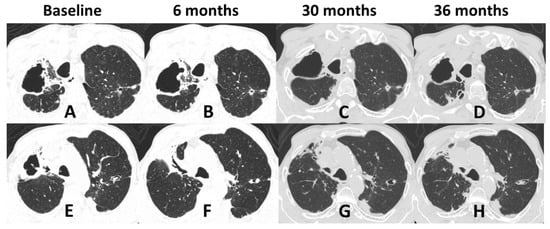

3.3. Radiological Patterns

| 1 (2018) | Male | 71 | None | Primary pulmonary | Lungs | Alcoholism COPD | No | Reticulonodular infiltrate; cavitation; fibrosis Unilateral/Multilobar | Sputum; BAL | ITZ; PSZ | Under treatment |

| 2 (2018) | Male | 63 | Contact with cat | Disseminated | Lungs, bone | Alcoholism COPD | No | Cavitation; fibrosis; hilar lymphadenopathy Unilateral/Unilobar | Sputum; BAL | ITZ; AmB; PSZ | Under treatment |